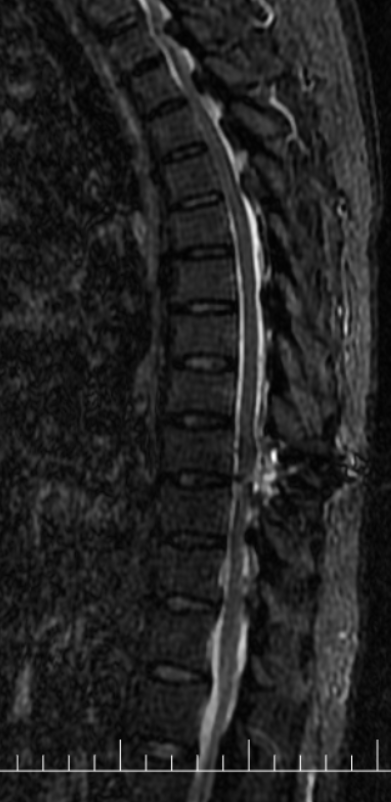

患者1+年前无明显诱因出现行走不稳症状,自诉有“踩棉感”,继而出行行走困难,近1+月明显加重,无法上下楼。对于一个居住在5楼(步梯)的患者来说,出门也变成了奢望。患者曾因为此症状反复就诊于省内外多家三甲医院,因体征不典型及相对复杂的既往史,曾被考虑为“糖尿病周围神经病变”、“焦虑症”等,长达1+年的治疗并没有使症状得到改善,反而逐渐加重,行走都只能靠助行器,甚至弯腰拾物简单的动作都不能执行,抱着尝试再一下的心态,患者就诊于我院,以椎管狭窄收入病房。入院早期因患者既往“焦虑症”的诊断,以及症状体征的不典型也给我科医务工作者在考虑诊断时造成了误导,经过反复积极查体考虑椎管狭窄,于是积极完善了脊柱的影像学检查,颈椎间盘、胸部及腰椎间盘CT:1、颈椎退行性变并颈椎椎管明显狭窄、颈2-3左侧椎间孔变窄;2、胸椎退行性变并胸1-7节段椎管轻度狭窄。胸腰椎MRI回示:1、颈椎退行性变并颈1-7水平后纵韧带增厚、钙化,继发椎管节段性狭窄。2、胸椎多段黄韧带增厚、钙化,继发相应椎管狭窄,脊髓节段变性(胸1-2及胸9-10水平)。结果出来后医生犯难了,问题找到的同时发现狭窄的地方及位置太多了,对于这种颈胸椎多处狭窄的病人想通过一个手术去解决几乎是不可能事情,针对此种情况,科内医师多次病例讨论,结合患者影像学检查、症状及体征,瞄准了T9-10平面的巨大黄韧带骨化。

此处黄韧带骨化严重,脊髓压迫严重,椎管狭窄处约只有4mm。考虑到手术难度较大,传统麻醉下手术瘫痪风险甚至可达20%以上,2022年6月24日科室内部邀请医务部参与最终讨论,报请重大手术,并决定使用局部麻醉与全凭静脉麻醉联合,保持术中唤醒随时检查下肢运动功能的麻醉方式,利用椎间孔镜可以直视的优点,行椎间孔镜下胸椎后路T9-T10椎板切除减压、黄韧带摘除、脊神经探查松解术。在2022年6月25日经过长达4小时20分钟的精细操作下最终将患者的压迫解除。几乎完整取出了巨大的骨化黄韧带。

术后积极控制血糖、血压,预防并发症,术后复查见: